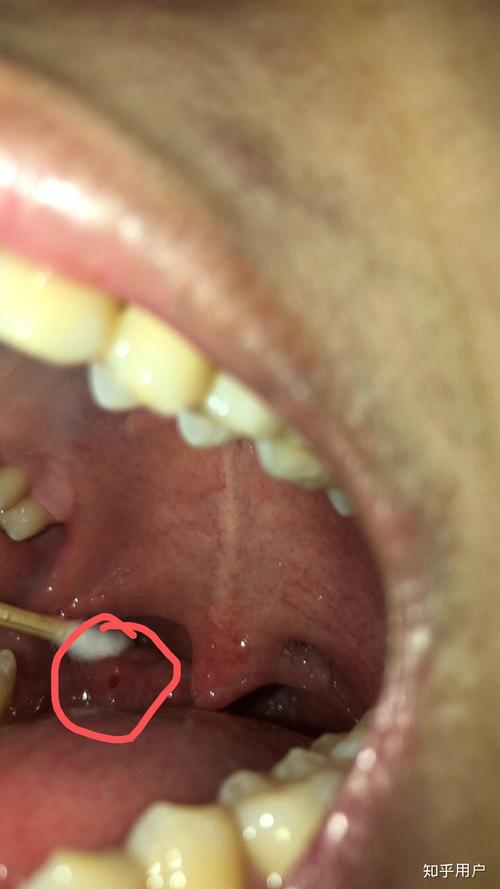

如果你的黄颗粒主要出现在喉咙两侧,那就要考虑是不是扁桃体结石了。

它是什么? 扁桃体表面有许多凹陷的“隐窝”,当食物残渣、脱落的细胞和细菌在这些隐窝内堆积、钙化后,就会形成黄白色或黄褐色的、质地坚硬的颗粒状物,这就是扁桃体结石。

典型症状:

- 感觉喉咙有异物感,咳不出来咽不下去。

- 持续的口臭,是扁桃体结石最典型的伴随症状。

- 有时会引起反复的咽喉疼痛或扁桃体发炎。

如何判断? 对着镜子张开嘴,压住舌头,用光照射喉咙两侧,有时能肉眼看到白色或黄色的“小石子”。